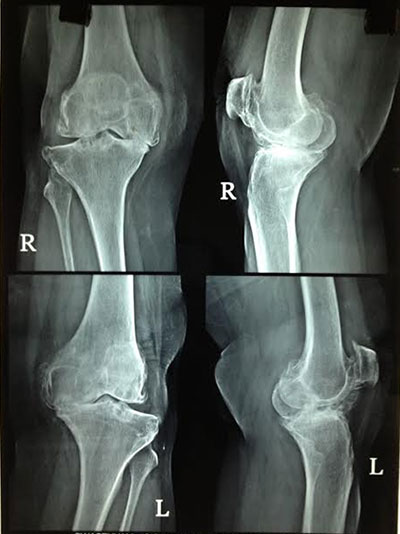

Total Knee Replacement

Knee Replacement